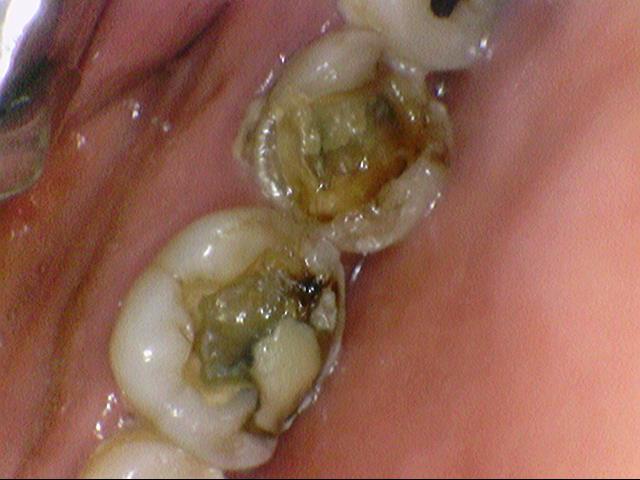

이런식으로 파절된 치아, 충치치아도 많았구요.

아래쪽 큰 어금니는 파절되고 썩어있는 상태였습니다.